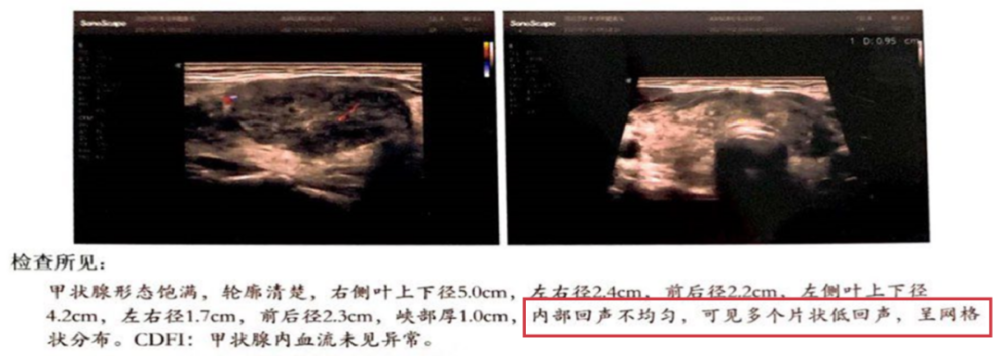

2 型:整个甲状腺腺体回声减少,偶尔可见小片高回声组织镶嵌分布其中,呈「孤岛样」改变,这是少数未被侵袭的正常组织。(见下图)

二维灰阶段纵断面显像,病灶累及广泛,仅见少量正常组织,甲状腺形态饱满。

图源:甲状腺疾病超声诊断图谱